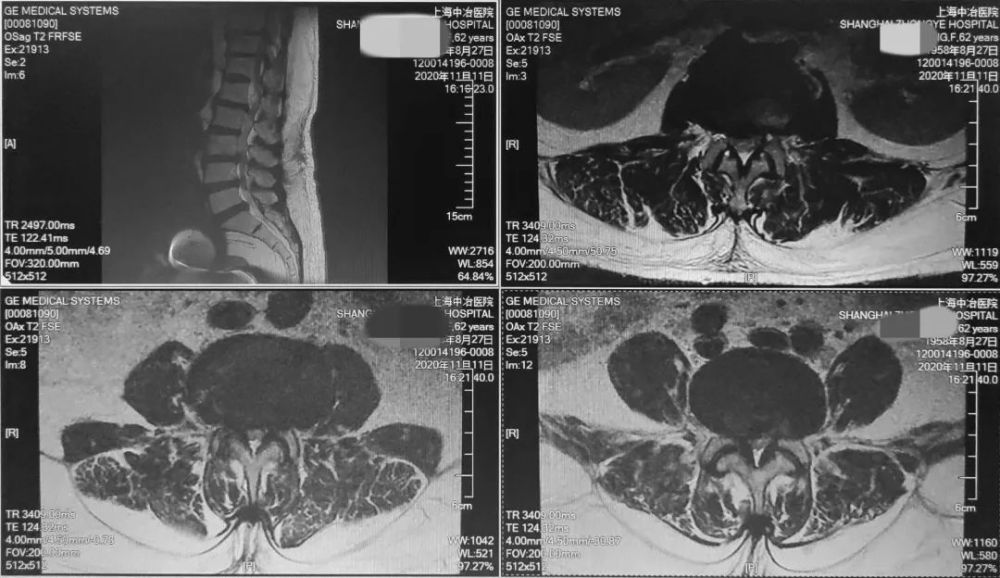

核磁共振MRI

可提供腰椎管的矢状面、冠状面和轴位横断面上的影像 。 椎管狭窄以T2加权像显示较好 , 脑脊液为高信号 , 产生所谓“脊髓造影”的效果 , 而骨质增生 , 骨赘、间盘均为低信号 , 能清晰地显示椎管狭窄 , 以及对脊髓的压迫情况 。 但对肥大的黄韧带、骨质增生等的判断则不如较高清晰度CT扫描 。

文章插图